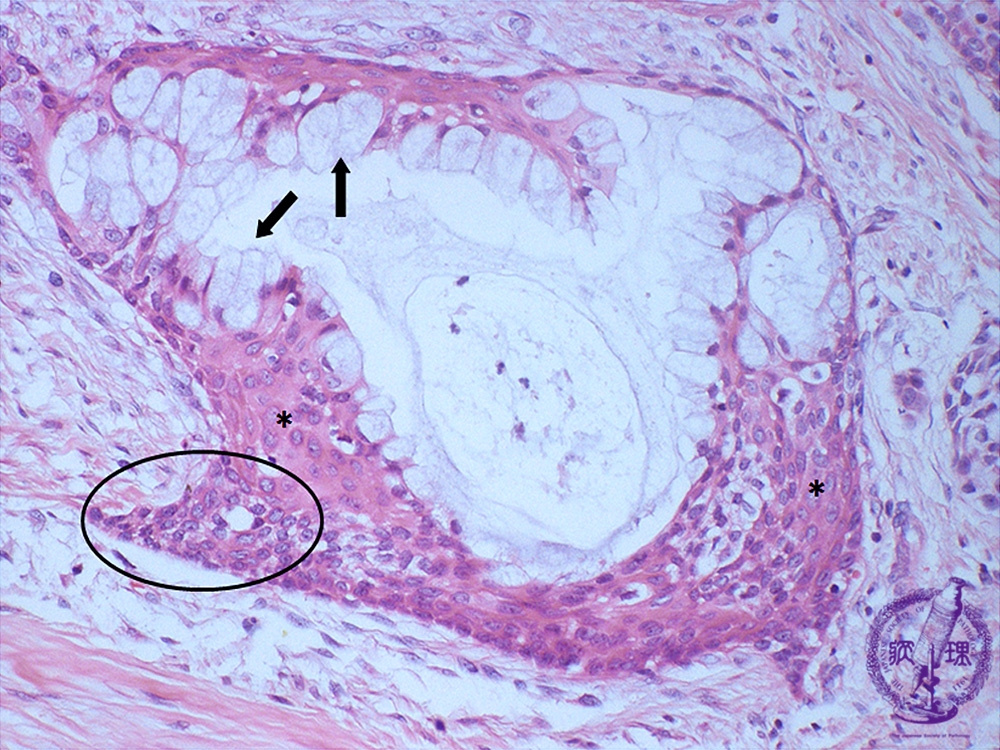

唾液腺腫瘍(粘表皮癌)ミクロ像(HE強拡大)

ミクロ像(HE強拡大):粘液産生細胞(矢印)と類表皮細胞(*)が主体で、細胞異型や分裂像には乏しい。分化の明らかでない小型の中間細胞(円内)も少数認められる。